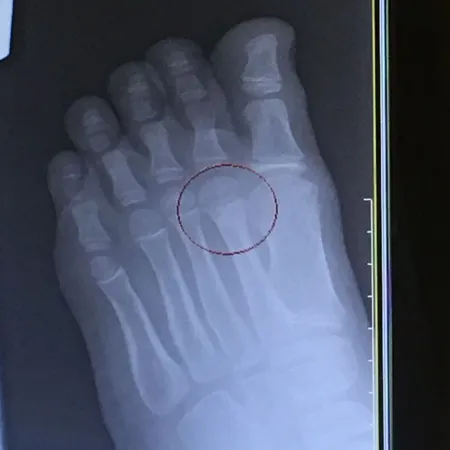

Pediatric Displaced 5th Met Distal shaft/neck fracture

Preop Pics of the displaced fracture prior to Percutaneous Fixation and Reduction

We percutaneously put a pin across the fracture after closed reduction for 12-16 weeks. The last picture is a final after the fracture is healed and the pin is removed.